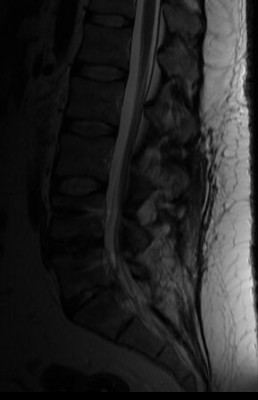

Nyakamon kicsik de sok van,

Hátamba kettő, ebből az alsó eléri a gerincvelőt,

Derekam szanaszét trancsírozva, foramen szűkületek, deformált, stb,

Legutóbbi rtg. idegsebész elismerte hogy a felvételen is látszik az erősen jobbra dőlő gerinc kénszertartása, ami a fájdalmat jelzi és hogy baj van. De hogy mi a baj azt nem tudja.Hogy ezekből ki mit látott meg ki mit nem, azt nem tudom. De ha műteni akarnak nem fogok bele egyezni. Elég volt a segítségükből.

elég érdekes, mri-t jó lenne látni, mégis mi az, ami nem utal műtétre, de gondot okoz.

mi nyomja akkor az ideget? a csavarok? -